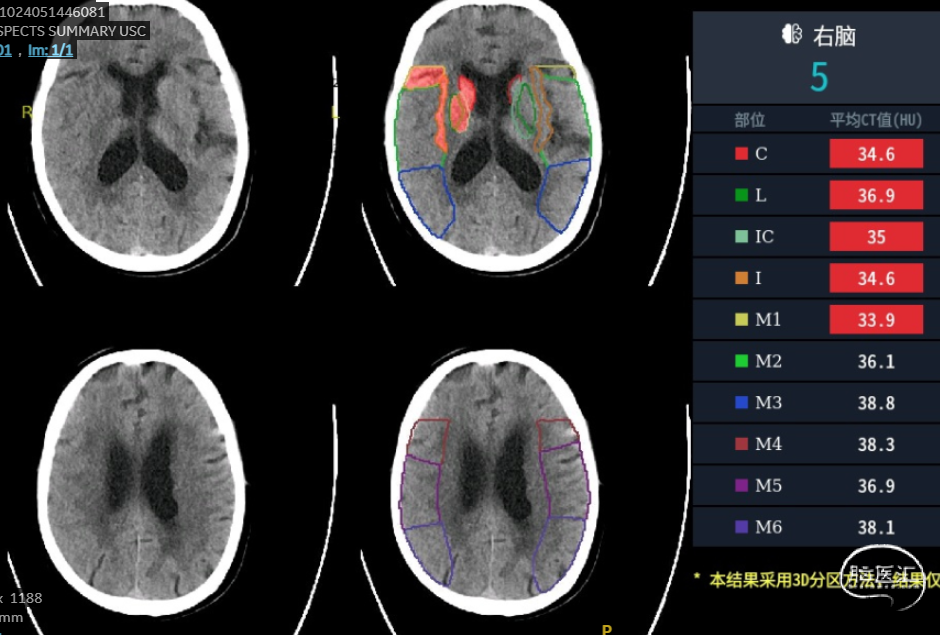

影像信息

CT平扫(ASPECT评分及CTP灌注)。

头颅及颈部血管:右侧颈内动脉起始部重度狭窄狭窄、颈内动脉末端闭塞,考虑房颤导致的颈动脉串联栓塞。